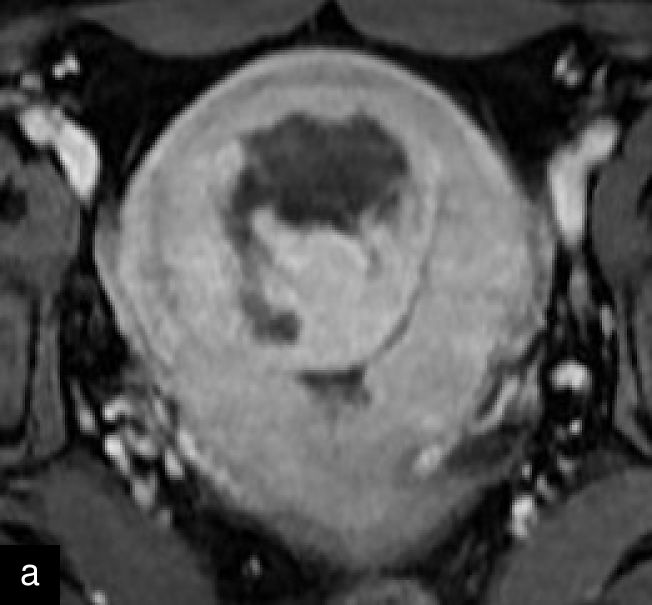

Magnetic resonance imaging (MRI) may help in the preoperative evaluation of uterine masses, when ultrasound findings are inconclusive. MRI offers higher accuracy in soft-tissue contrast, a larger field of view, diffusion imaging and multiplanar capabilities.15 A recent consensus statement has provided a standardized approach to MRI assessment, emphasizing its role in distinguishing uterine sarcomas/STUMP from benign leiomyomas.15 Features suggestive of malignancy include irregular margins; heterogeneous and high signal on T2 weighted imaging; and hemorrhagic and necrotic changes, with central non-enhancement, hyperintensity on diffusion-weighted imaging (DWI), and low values for apparent diffusion coefficient (ADC)15,25,39,40,41 (Figure 7). Diagnostic algorithms have been proposed to support MRI interpretation in differentiating between benign and malignant uterine lesions, and recent studies have explored the use of artificial intelligence to further enhance diagnostic accuracy.42,43,44 Emerging technologies, including radiomics and machine learning, show promise in improving diagnostic precision, although standardization and external validation remain essential.39,45

7

Magnetic resonance imaging (MRI) of a STUMP. (a) Contrast-enhanced MRI showing heterogeneous enhancement of the mass. (b) T2-weighted MRI demonstrating a hyperintense lesion with heterogeneous signal intensity. (c) Diffusion-weighted imaging (DWI) highlighting areas of restricted diffusion. (d) Apparent diffusion coefficient (ADC) map, showing low ADC values suggestive of increased cellularity, aiding in the differentiation of STUMP from benign leiomyomas and malignant leiomyosarcomas.